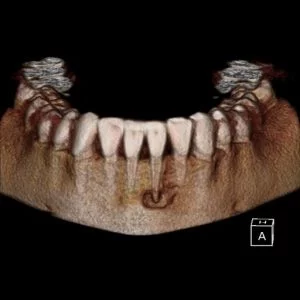

Second, I was able to utilize the dramatic effect of such a high resolution volume to educate the patient in a clear and compelling way.   I was able to stress the importance of taking care of this situation.

A CBCT was taken after a negative cold test indicated a necrotic tooth.  When the CBCT was taken, we could clearly see that the abscess had completely perforated the labial bone at the apex of #24 and was close to doing so on #25.

As we investigated more deeply, we identified another critical piece of information that would affect our treatment plan: a second canal on #24.